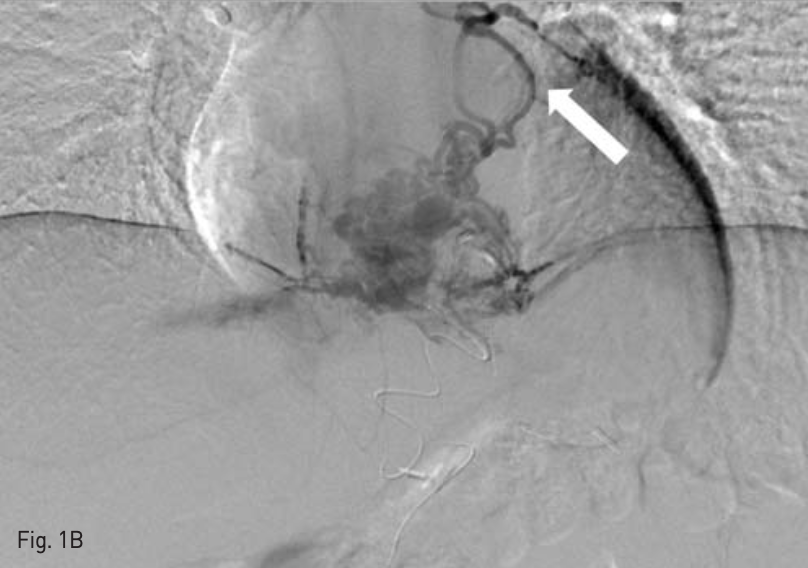

이후 feeder를 microcatheter(Progreat, Terumo, Tokyo, Japan)및 microwire(Transcend. Cook medical, Bloomington, IN, USA)를 이용하여 selection하여 1:5 and 1:8 NBCA - lipiodol mixture를 이용하여 embolizalion 시행하였는데, 소량의 NBCA - lipiodol mixture가 pulmonary artery로 migration한 것이 보였다(Fig. 1B).

B. Venography performed from the microcatheter which was located at the proximal side of esophageal varix, shows PPVA (arrow), which was a dilated vessel running cranially and is connected to the left inferior pulmonary vein.